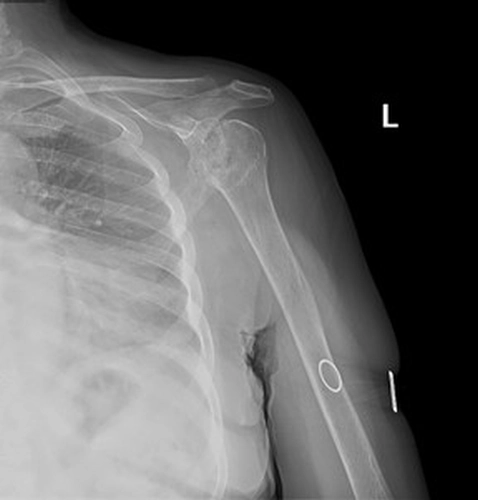

Şikayet:Sol omuzda hareket kısıtlılığı.

Özgeçmiş:10 yıl önce yaygın eklem ağrıları olan hasta RA tanısı almış KS ve MTX kullanım öyküsü mevcut hasta kortikosteroid ile takipli.

Muayene:Sol omuz: Flex: 0-70°, Abd: 0-70°, İstirahatte VAS: 0, Hareket ile VAS:1-2, GYA’de bağımsız. Sistemik tutulum ve organ tutulumu yok. Diğer fizik muayene doğal ellerde deformite yok.

Sol Omuz MRG: Glenoidde kortikal düzensizlikler, lokalize defektif alanlar ve bu düzeyde subkondral milimetrik kistlerin eşlik ettiği medüller hafif hiperintens ödem izlenmektedir. Humerus baş kesiminde medialde de geniş bir alanda defektif görünüm mevcuttur. Buna komşu humerus başında milimetrik kistler ve medüller ödem izlenmektedir.

Humerus başında ve glenoid de osteofitik dejeneratif değişiklikler mevcuttur. Gleno-humeral eklem aralığı anterior inferiorda daralmıştır.Eklem aralığında sıvı miktarında belirgin artış izlenmedi.

Humerusta tüberkülüm majusta milimetrik kist - medüller ödem benzeri sinyal değişikliği dikkati çekmektedir.

Akromioklaviküler eklemde minimal dejeneratif hipertrofi izlenmekte olup eklem aralığı yaklaşık 5 mm ölçülmüştür ve normal sınırlar içerisindedir. Subakromial yağ mesafesi basılıdır. Akromion Tip 2 konfigürasyondadır. Glenoid labrumlar değerlendirilemedi. Biceps uzun başı tendonu normaldir. Supraspinatus tendonunda tendinozis izlenmektedir.

Resim 1

Ön tanıda romatoid artrite bağlı eklem tutulumu, avasküler nekroz, Charcot eklemi (periferik nöropati- servikal radikülopati?) olasılıkları tartışıldı. Hastanın ileri derecedeki eklem kısıtlılığı ve buna bağlı gelişen omuz çevresi kaslarda atrofisi olması sebebi ile artroplastiden fayda görebileceği öngörüldü.